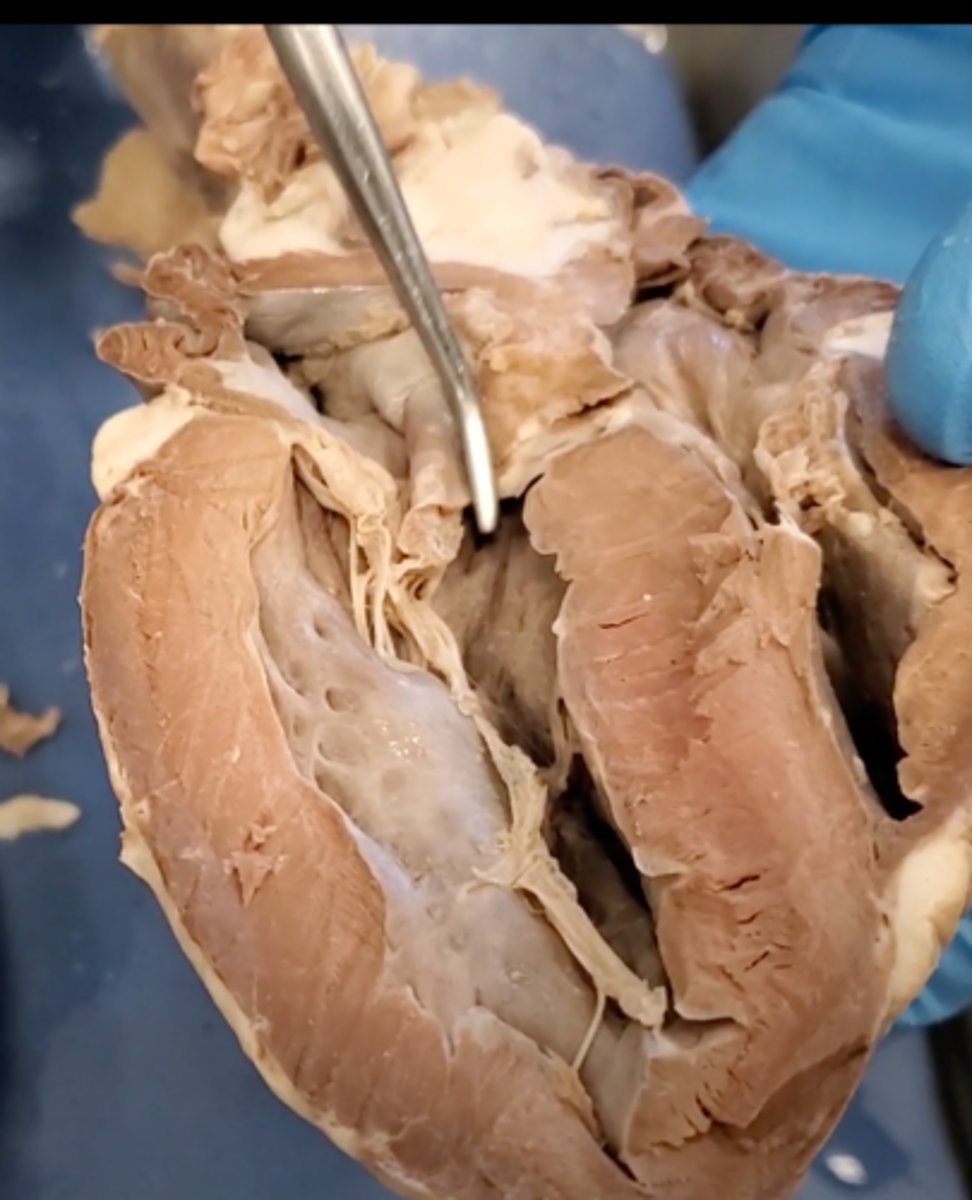

Tricuspid Valve (Right Atrioventricular Valve)

1-valve

Bicuspid valve (Left Atrioventricular Valve)

2-valve

Pulmonary Semilunar Valve

3-valve

Aortic Semilunar Valve

4-valve

Right Atrium

1-chamber

Left Atrium

2-chamber

Right Ventricle

3-chamber

Left Ventricle

4-chamber

bicuspid valve (dissection)

tricuspid valve (dissection)

aortic semilunar valve (dissection)

located between the left ventricle and the aorta

chordae tendineae (dissection)

thin bands of fibrous tissue that attach to the valves in the heart and prevent them from inverting